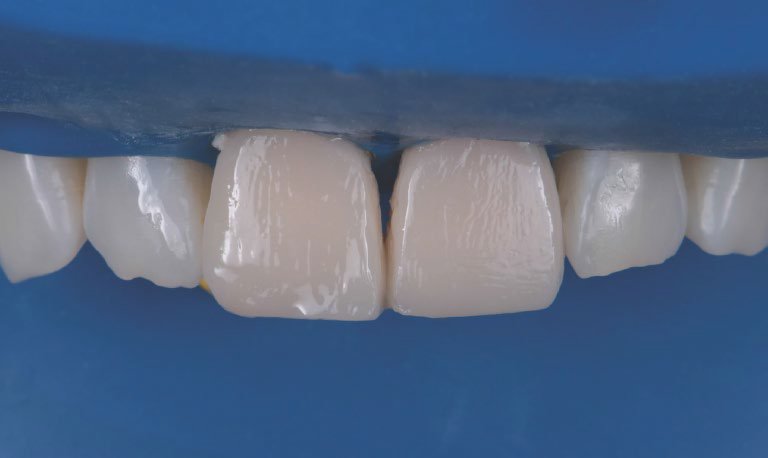

Restorations after polishing using the 3M™ Sof-Lex™ Diamond Polishing System.